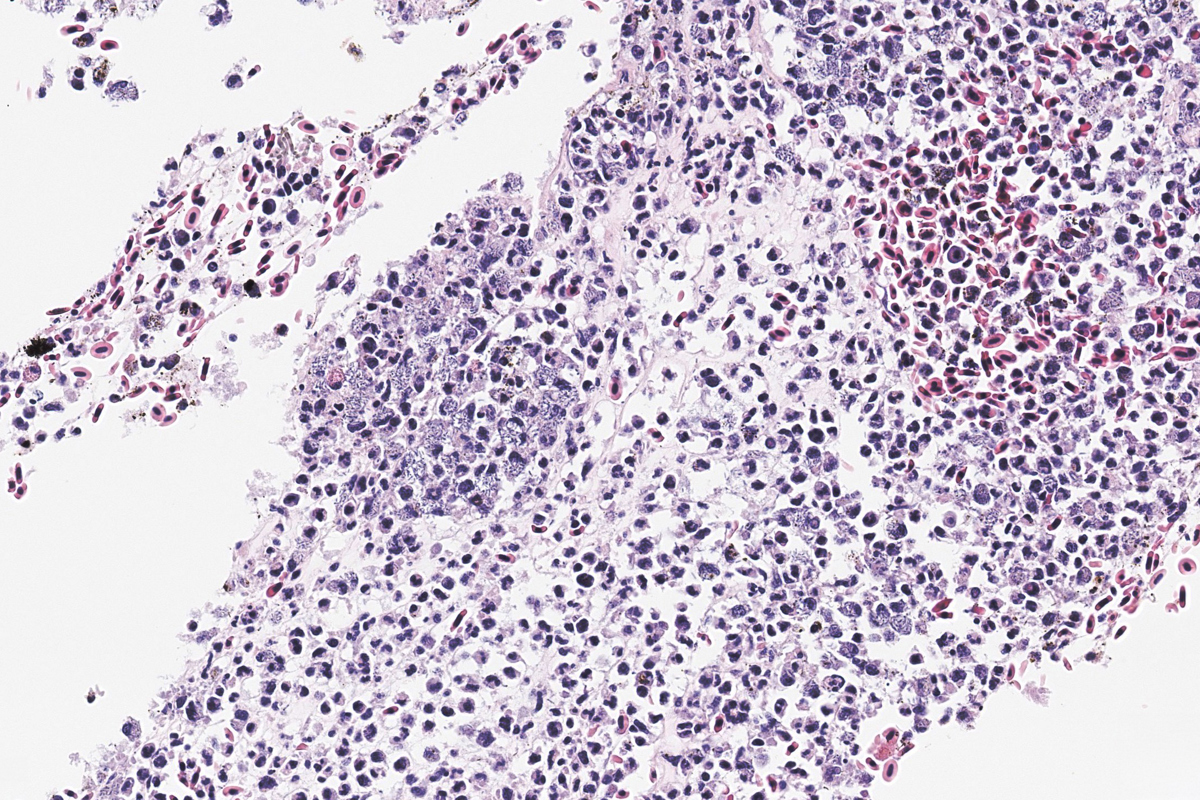

Vibriose er en sykdom som rammer mange ulike fiskearter, både villfisk og oppdrettsfisk i sjøvann og brakkvann. Sykdommen forårsakes av bakterier i slekten Vibrio, og utbrudd skjer ofte i forbindelse med stress, for eksempel ved håndtering, og særlig når vanntemperaturen er høy.

Vaksine mot Vibrio anguillarum gir vanligvis god beskyttelse. Likevel kan det forekomme sykdomsutbrudd, spesielt under ugunstige forhold.

I 2024 ble det rapportert enkelte tilfeller av vibriose hos regnbueørret. Det ble påvist systemiske infeksjoner med V. anguillarum, men i de fleste tilfellene var det en bakterie som lignet V. ordalii som dominerte.

Det kliniske bildet viste økt dødelighet, hudblødninger og tegn til sepsis med petekkier i flere organer. Det er også vanlig med utflytende milt ved vibriose hos regnbueørret.

Bilde 3: Histologisk snitt. HE-farging. Hud med bakteriell dermatitt (pil), fra en sak med påvist klassisk vibriose.